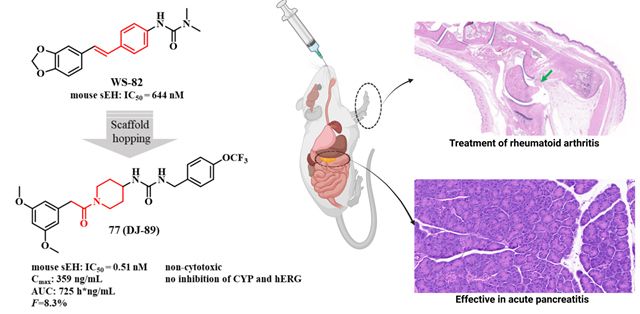

風濕性關節炎等慢性炎癥性疾病因高致殘率和現有藥物副作用大、療效不穩定等問題,而胰腺炎目前臨床沒有有效藥物,長期面臨治療困境。sEH在炎癥調控中至關重要,它代謝體內的有益的抗炎因子—環氧二十碳三烯酸,促使炎癥發展,成為抗炎藥物研發熱門靶點。不過,此前進入臨床II期試驗的sEH抑制劑,因藥代動力學缺陷或安全性問題折戟,目前沒有任何藥物被批準上市。這一現狀使得開發具有全新化學骨架的藥物變得尤為迫切,也極具重要意義。此前,我們設計了多種骨架的sEH抑制劑( European Journal of Medicinal Chemistry 2024, 266, 116113; European Journal of Medicinal Chemistry 2024, 280.; Journal of Medicinal Chemistry 2024, 67, 18412?18447; Journal of Medicinal Chemistry 2024, 67, 22168-22190.)。此次,我們基于“骨架躍遷”策略,從天然二苯乙烯衍生物出發,設計合成了九種新型骨架化合物,最終篩選出以“苯乙酰哌啶”為核心骨架的DJ-89。該藥物在多項實驗中表現出色:1)超強抑制活性:DJ-89對sEH的抑制活性(IC50 = 0.51 nM)比臨床候選藥EC5026(19 nM)和TPPU(44 nM)高數十倍。2)獨特抗炎機制:通過提升EETs水平并降低其代謝產物DHETs,DJ-89顯著抑制促炎因子(TNF-α、IL-1β)水平,同時增加抗炎因子IL-10水平,這一“雙效調節”機制具有創新性。3)體內顯著療效:在類風濕性關節炎大鼠模型中,DJ-89(10 mg/kg口服)有效減輕關節腫脹和骨侵蝕;在急性胰腺炎模型中,其抑制胰腺組織的炎癥細胞浸潤效果突出,同時血漿IL-6水平下降50%。4)優異的安全性:對hERG和CYP酶影響微弱,大幅降低臨床用藥風險。5)藥代動力學良好:口服生物利用度達8.3%,半衰期1.89小時,且主要富集于sEH表達量高的肝、腎部位,腦部暴露量低,預示其全身抗炎作用顯著且中樞副作用風險小。

圖2 在急性胰腺炎模型中化合物77(DJ-89)的治療效果